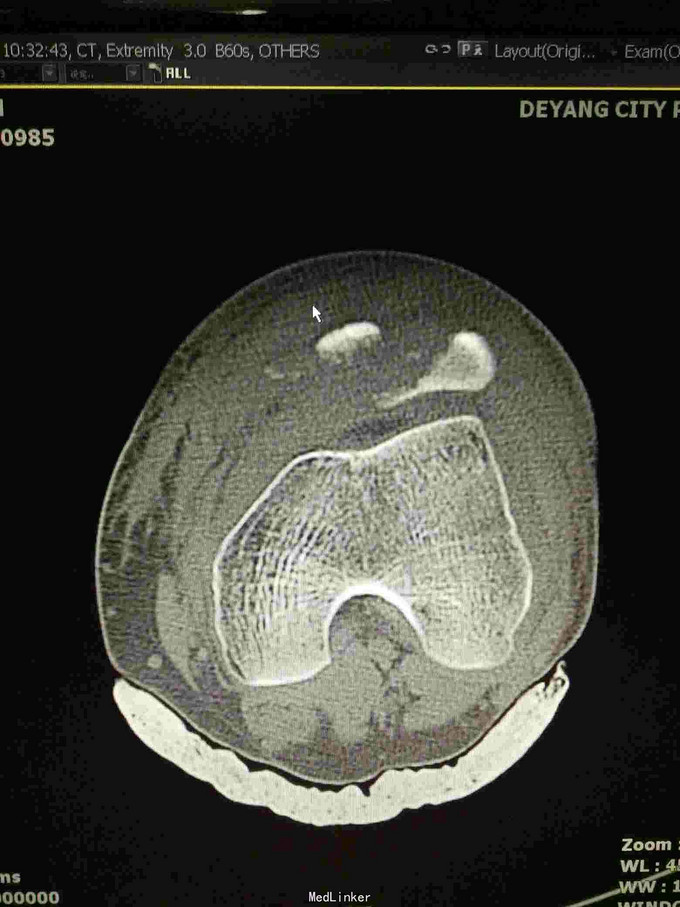

左髌骨粉碎性骨折

查体:左下肢活动受限,背伸障碍,左膝关节明显肿胀,压痛,扪及骨擦感,左足感觉及血循环可。 x片:左髌骨骨折。

诊断:左髌骨粉碎性骨折; 治疗,石膏固定,消肿止痛,行髌骨骨折切开复位克氏针内固定术,术中克氏针张力带钢丝固定,术后石膏固定。